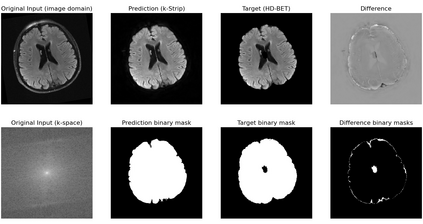

Objectives: Present a novel deep learning-based skull stripping algorithm for magnetic resonance imaging (MRI) that works directly in the information rich k-space. Materials and Methods: Using two datasets from different institutions with a total of 36,900 MRI slices, we trained a deep learning-based model to work directly with the complex raw k-space data. Skull stripping performed by HD-BET (Brain Extraction Tool) in the image domain were used as the ground truth. Results: Both datasets were very similar to the ground truth (DICE scores of 92\%-98\% and Hausdorff distances of under 5.5 mm). Results on slices above the eye-region reach DICE scores of up to 99\%, while the accuracy drops in regions around the eyes and below, with partially blurred output. The output of k-strip often smoothed edges at the demarcation to the skull. Binary masks are created with an appropriate threshold. Conclusion: With this proof-of-concept study, we were able to show the feasibility of working in the k-space frequency domain, preserving phase information, with consistent results. Future research should be dedicated to discovering additional ways the k-space can be used for innovative image analysis and further workflows.